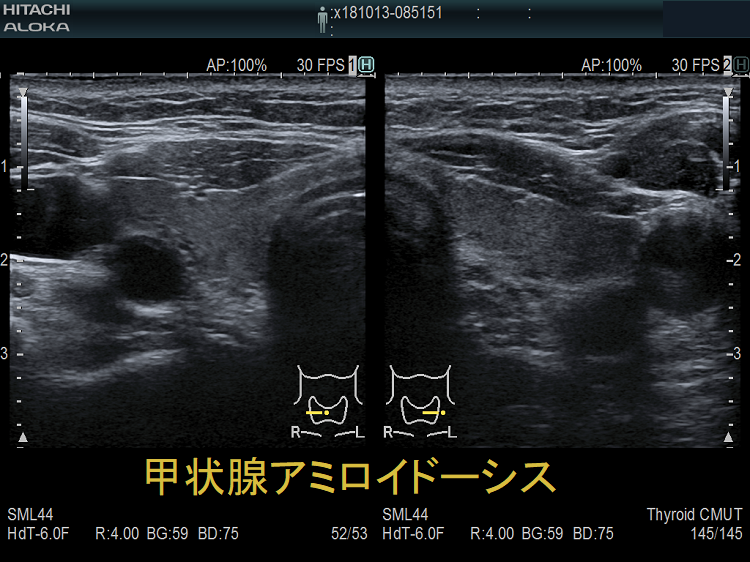

アミロイドーシスは線維構造をもつ不溶性蛋白のアミロイドが臓器に沈着し機能障害をおこす疾患。原発性甲状腺アミロイドーシスは稀。結節性甲状腺アミロイドーシスは橋本病のリンパ球・形質細胞がIgGκ鎖を産生するのが原因?多発性骨髄腫のM蛋白によるALアミロイドーシス、関節リウマチの血清アミロイドA(SAA)によるAAアミロイドーシス、トランスサイレチン型家族性アミロイドポリニューロパチーもある。症状は甲状腺機能低下症、難治性下痢、ネフローゼ症候群。甲状腺超音波(エコー)画像は高輝度/低輝度いずれもあり。穿刺細胞診で無構造好酸性物質を認めコンゴーレッド染色陽性。

謎の結節性甲状腺アミロイドーシスを鹿児島大学が甲状腺学会で複数回、さらに大分大学も論文で報告しています。超音波(エコー)検査上、見かけは甲状腺腫瘍、境界不明瞭・不均質な低エコー領域で、石灰化も伴う。穿刺細胞診で腫瘍成分はなく、アミロイドのみが見つかるも、アミロイドーシスをおこす他の病気が全くないとの事です。

甲状腺アミロイドーシスの症状は、

- びまん性甲状腺腫大(amyloid goiter、アミロイド ゴイター):アミロイドが甲状腺に沈着し、甲状腺は腫大します。多発性骨髄腫が原因のALアミロイドーシスでは化学療法により甲状腺腫が縮小します

- 甲状腺機能低下症;アミロイド沈着による甲状腺濾胞組織の破壊が原因

甲状腺アミロイドーシス(関節リウマチ)母娘